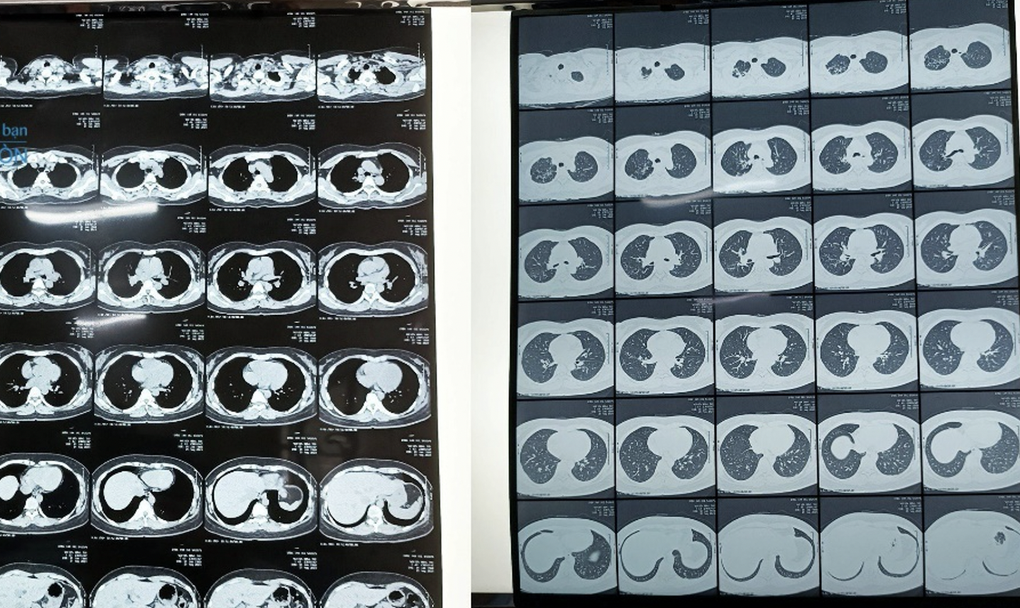

Ảnh chụp CT scan của bệnh nhân T. ngày 21/8 (Ảnh: BV).